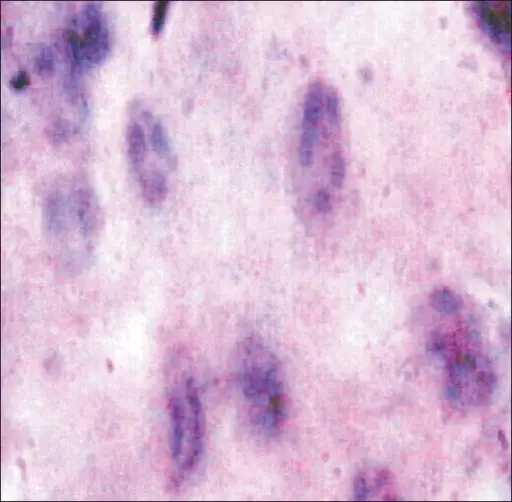

Squamous Cell Carcinoma

Squamous cell carcinoma (SCC) is the second most frequently diagnosed cancer worldwide.

Squamous cell carcinoma (SCC) accounts for about 30% of cancer cases in men and 20% of cases in women.

Two important risk factors for squamous cell carcinoma (SCC) are alcohol and tobacco use.

Invasive squamous cell carcinoma (SCC) may develop from oral leukoplakias and erythroplakias, which are precancerous diseases.

Although they can appear anywhere in the oral cavity epithelium, these lesions typically grow at the mouth’s floor.

Histologically, squamous cell carcinoma (SCC) is identified by alterations in the stratified squamous epithelial layers, such as invasion into the underlying connective tissue and hyperkeratosis, parakeratosis, acanthosis, keratin pearls, and dysplasia.